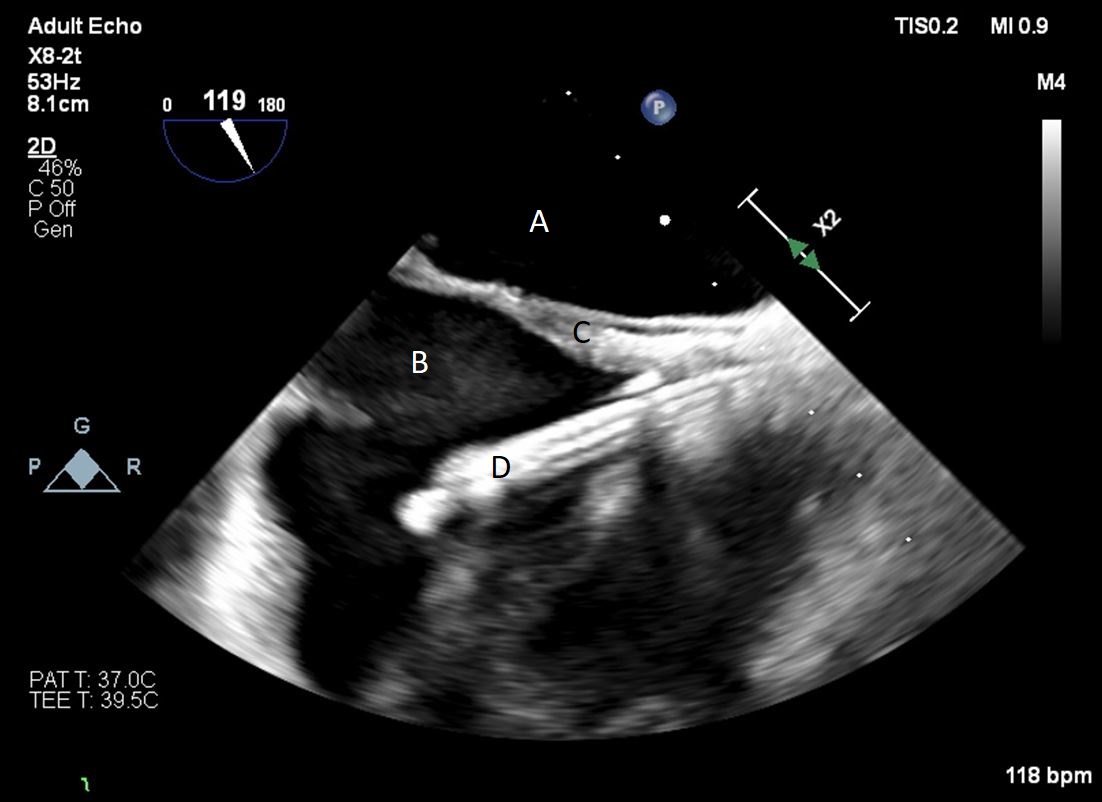

The TandemHeart Protek Duo is a percutaneous right ventricular assist device (RVAD) placed via a dual-lumen 29 French sheath in the right internal jugular vein. The inflow lumen is situated in the right atrium and outflow lumen in the main pulmonary artery. The port lumens are connected externally to a TandemHeart centrifugal pump [31]. As this is generally placed in the operating room, intra-operative TEE can be used to help guide placement. Similar to the Impella RP, bicaval and midesophageal 4 chamber views can visualize the inflow cannula and RV inflow-outflow view and upper esophageal views can be used to visualize the outflow cannula (Figs. 13,14,15). On occasion, its placement can result in distortion of the tricuspid valve morphology with resultant tricuspid regurgitation (Fig. 16). If this is noted, cannula repositioning can be considered. TEE can also help in identifying the ideal pump speed for a patient on TPD support. When utilizing a “ramp protocol”, where the pump speed is progressively increased intraoperatively, midline interventricular septal position can indicate an appropriate amount of RV support [32].

Fig. 13.A bicaval view on a TEE done during placement of a Protek Duo. The inflow lumen is seen entering the right atrium from the SVC. (A) Left atrium. (B) Right atrium. (C) Interatrial septum. (D) Protek Duo inflow lumen.